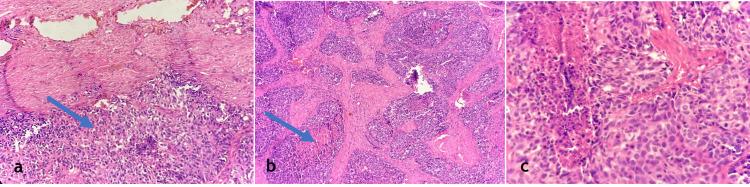

Malignant priapism is a rare and serious manifestation that results from advanced malignancy. It is caused by the infiltration of tumour cells into the penile tissue. Genitourinary cancers are the most common cause, especially prostatic adenocarcinoma. It indicates widespread metastatic disease and is associated with a poorer prognosis. It presents as a prolonged, painful erection that is not related to sexual activity and is often refractory to conventional treatments. It is rare and usually diagnosed late in the disease course. We report a 70-year-old male who underwent transurethral resection of the prostate (TURP) and bilateral orchidectomy for locally advanced prostatic adenocarcinoma and lost to follow-up. He presented six months later with painful priapism, multiple penile nodules, and acute urinary retention. Imaging studies, including high-resolution penile ultrasound and 18F-fluorodeoxyglucose positron emission tomography (18F-FDG PET) scan, confirmed multiple penile metastatic deposits. Despite initial pain management with nonsteroidal anti-inflammatory drugs (NSAIDs) and opioids, his refractory symptoms necessitated a total penectomy with perineal urethrostomy. Histopathological examination confirmed infiltrating carcinomatous deposits. Unfortunately, despite aggressive management, the patient eventually succumbed to the disease. This report emphasizes the aggressive character of penile metastases from prostate cancer, the challenges in diagnosis and treatment, and the need for a multidisciplinary approach. Early recognition and palliative strategies are essential for maximizing the quality of life.

恶性阴茎异常勃起是一种由晚期恶性肿瘤导致的罕见且严重的表现。它是由肿瘤细胞浸润阴茎组织引起的。泌尿生殖系统癌症是最常见的病因,尤其是前列腺腺癌。它表明存在广泛的转移性疾病,且预后较差。其表现为与性活动无关的持续性、疼痛性勃起,通常对传统治疗无效。它很罕见,且通常在病程晚期才被诊断出来。我们报告一例70岁男性,因局部晚期前列腺腺癌接受了经尿道前列腺切除术(TURP)和双侧睾丸切除术,之后失访。6个月后,他出现疼痛性阴茎异常勃起、多个阴茎结节及急性尿潴留。包括高分辨率阴茎超声和18F-氟脱氧葡萄糖正电子发射断层扫描(18F-FDG PET)在内的影像学检查证实阴茎有多处转移灶。尽管最初使用非甾体类抗炎药(NSAIDs)和阿片类药物进行了疼痛管理,但他的顽固性症状仍需要行全阴茎切除术与会阴尿道造口术。组织病理学检查证实有浸润性癌灶。不幸的是,尽管进行了积极治疗,患者最终仍死于该病。本报告强调了前列腺癌阴茎转移的侵袭性、诊断和治疗中的挑战以及多学科方法的必要性。早期识别和姑息治疗策略对于提高生活质量至关重要。